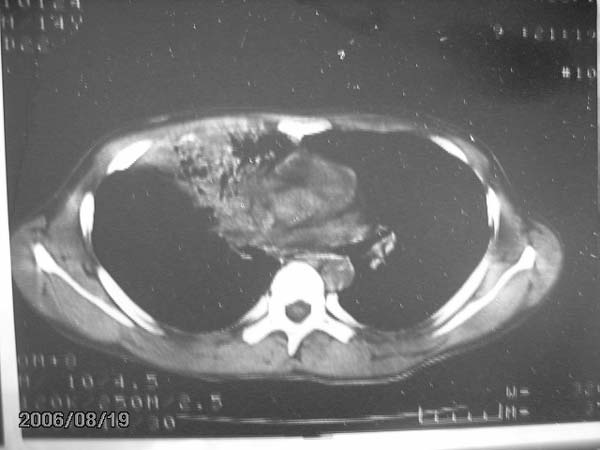

前段病变以炎症为多,应继续抗炎治疗,一般炎性病灶需1个月后才遂渐完全吸收。

灶内密度不均,似乎有囊状,条状影,考虑右中叶综合症; 从照片中看不出有无钙化灶,若明显则考虑结核性。

考虑中叶综合征(右肺门肿大淋巴结伴中叶阻塞性炎症)

谢谢大家的讨论,这个病人至今还没有做痰检,因为没痰.有了结果我一定通报